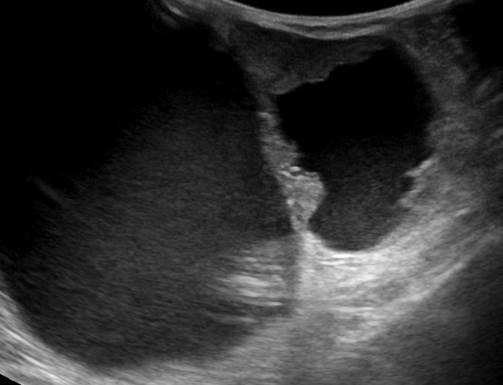

Ung thư vú

» Thông tin: Nữ giới – 85 tuổi.

» Lâm sàng: Khối tuyến vú.